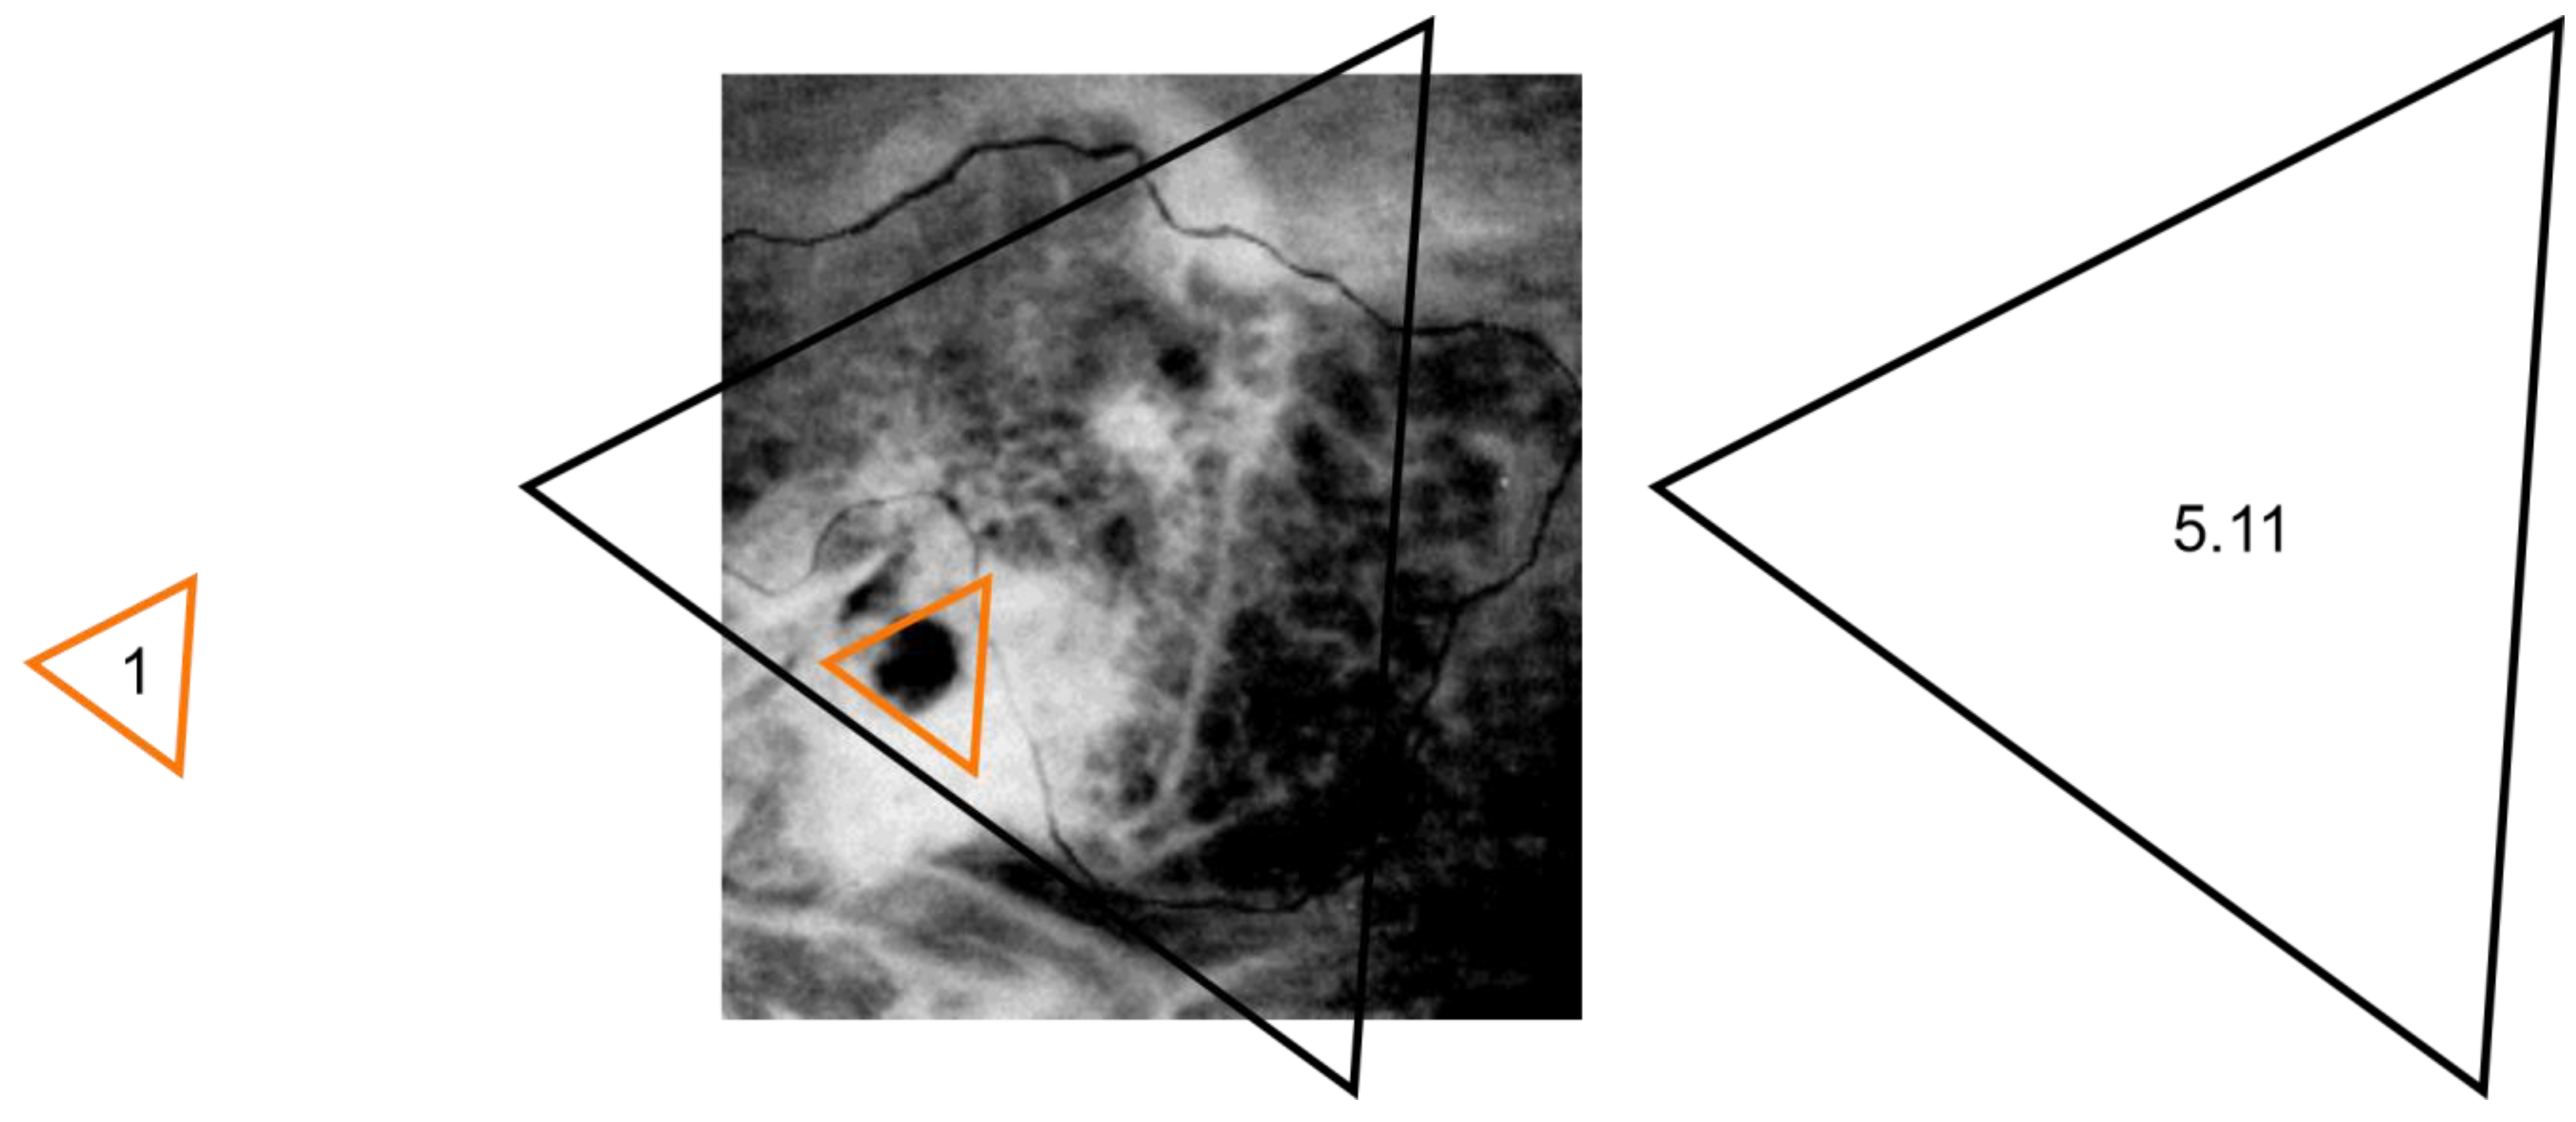

Figure 12.

URCOTEBS_a. The measuring gauge and the projection area of the Anatomic Macroscopic Radiopaque Peripheral Support of the D-Organ superimposed on the radiographic image of the TB. In the case of a URCOTEBS_a, the projection area has a mean value 5.11 times larger than the gauge area (see Table 4, column 7).